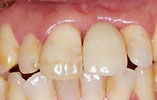

CASE4

上の前歯1本だけ失った場合 審美的回復

インプラント埋入前

インプラント埋入後

インプラントに

セラミッククラウンを装着

上の前歯1本だけ失った場合、通常両隣りの歯を削ってブリッジを入れますが、インプラント治療によって、健康な歯を削ることなく、審美的にも回復しました。。